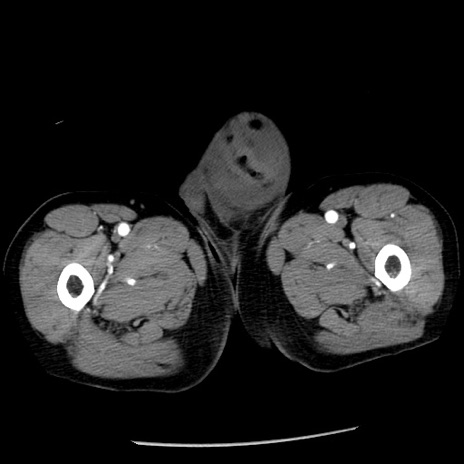

症例26(横断像)

【症例】80歳代男性

【主訴】嘔吐

【現病歴】昨晩2回嘔吐あり、今朝になっても嘔吐あり。来院。

【既往歴】胃潰瘍

【身体所見】意識清明、BT 37.6℃、BP 166/95mmHg、HR 100bpm、SpO2 97%、腹部:平坦・軟、腸蠕動音聴取良好、圧痛なし。

【データ】WBC 21900、CRP 1.46